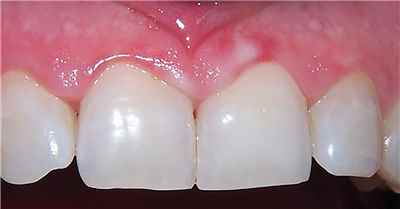

치아 변색 내부 원인

여드름 치료를 위해서 미노사이클린 복용으로 약간 파랗게 변색된 치아 (출처: Lee Ann Brady DMD)